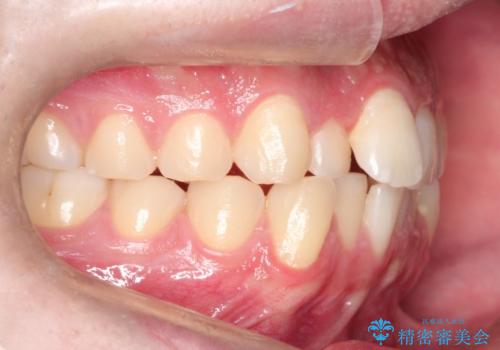

- 前歯の歯並びの改善を希望され来院された患者様です。

初診時の歯並びの状態としては、上下ともに前歯部の中等度以上のがたつき(叢生)があり、右の前歯が1本飛び出した状態でした。

抜歯は行わず上下顎ともに、主に歯列弓の拡大とディスキング(歯と歯の間に隙間を作る処置)を行い叢生を改善しました。